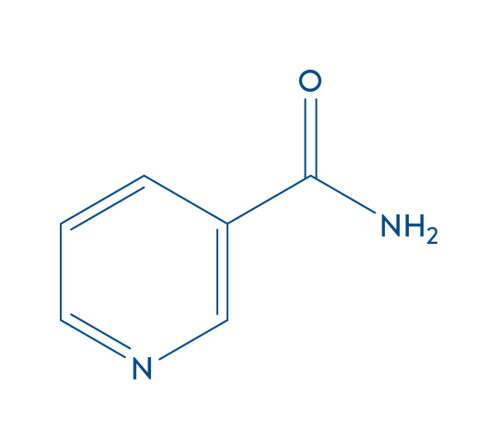

NIACINAMIDA

La niacinamida es una de las principales formas de vitamina B3 y se ha convertido cada vez más en un ingrediente buscado para muchos productos para la piel. Está clínicamente probado para ayudar a los efectos antienvejecimiento e hidratantes.

¿QUÉ ES LA NIACINAMIDA?

La niacinamida, también conocida como nicotinamida o niacina, es una de las principales formas de vitamina B3, una vitamina esencial requerida por el cuerpo humano para mantener una buena salud.